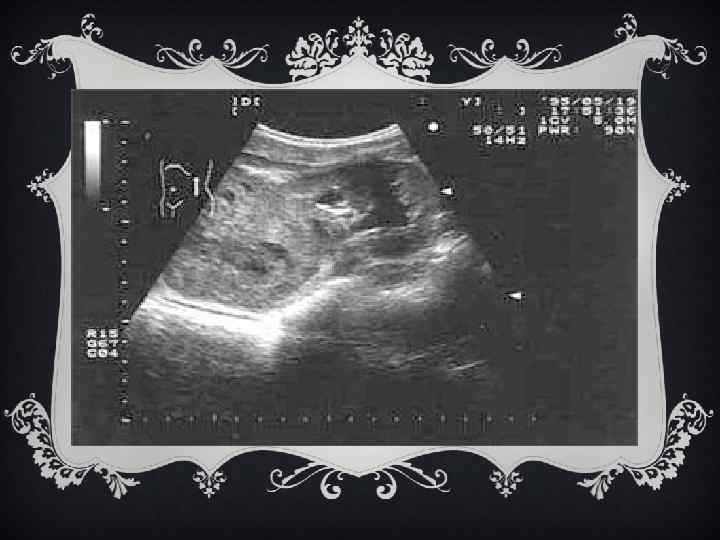

ДИАГНОСТИКА v УЗИ почки позволяет выявить объемное тканевое образование в почке, провести дифференциальную диагностику с кистозными образованьями. v Компьютерная томография брюшной полости и забрюшинного пространства является одним из самых точных методов выявления ОВ, оценки состояния регионарных лимфатических узлов и окружающих органов и тканей.